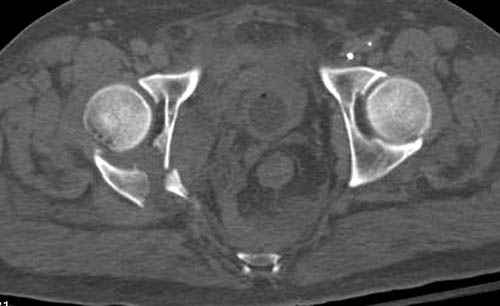

Дополнительно имеется перелом ацетабулума: задняя

колонна с полупоперечным переломом, и переломы костей лица.

На седьмой день зафиксирован перелом ацетабулума через задний доступ. Перед операцией для профилактики DVT, IVC фильтер, также получает Lovenox.